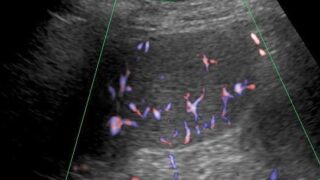

【DVTを見逃さない】下肢静脈エコー上達のコツ|描出安定・圧迫法・2-point法の考え方

下肢静脈エコーが難しいと感じていませんか?本記事では、圧迫法の基本、下腿3分枝の同定、DVTの好発部位、2-point法の考え方までを整理。初学者〜習得途中の技師さんに向けた実践的な上達のコツを解説します。